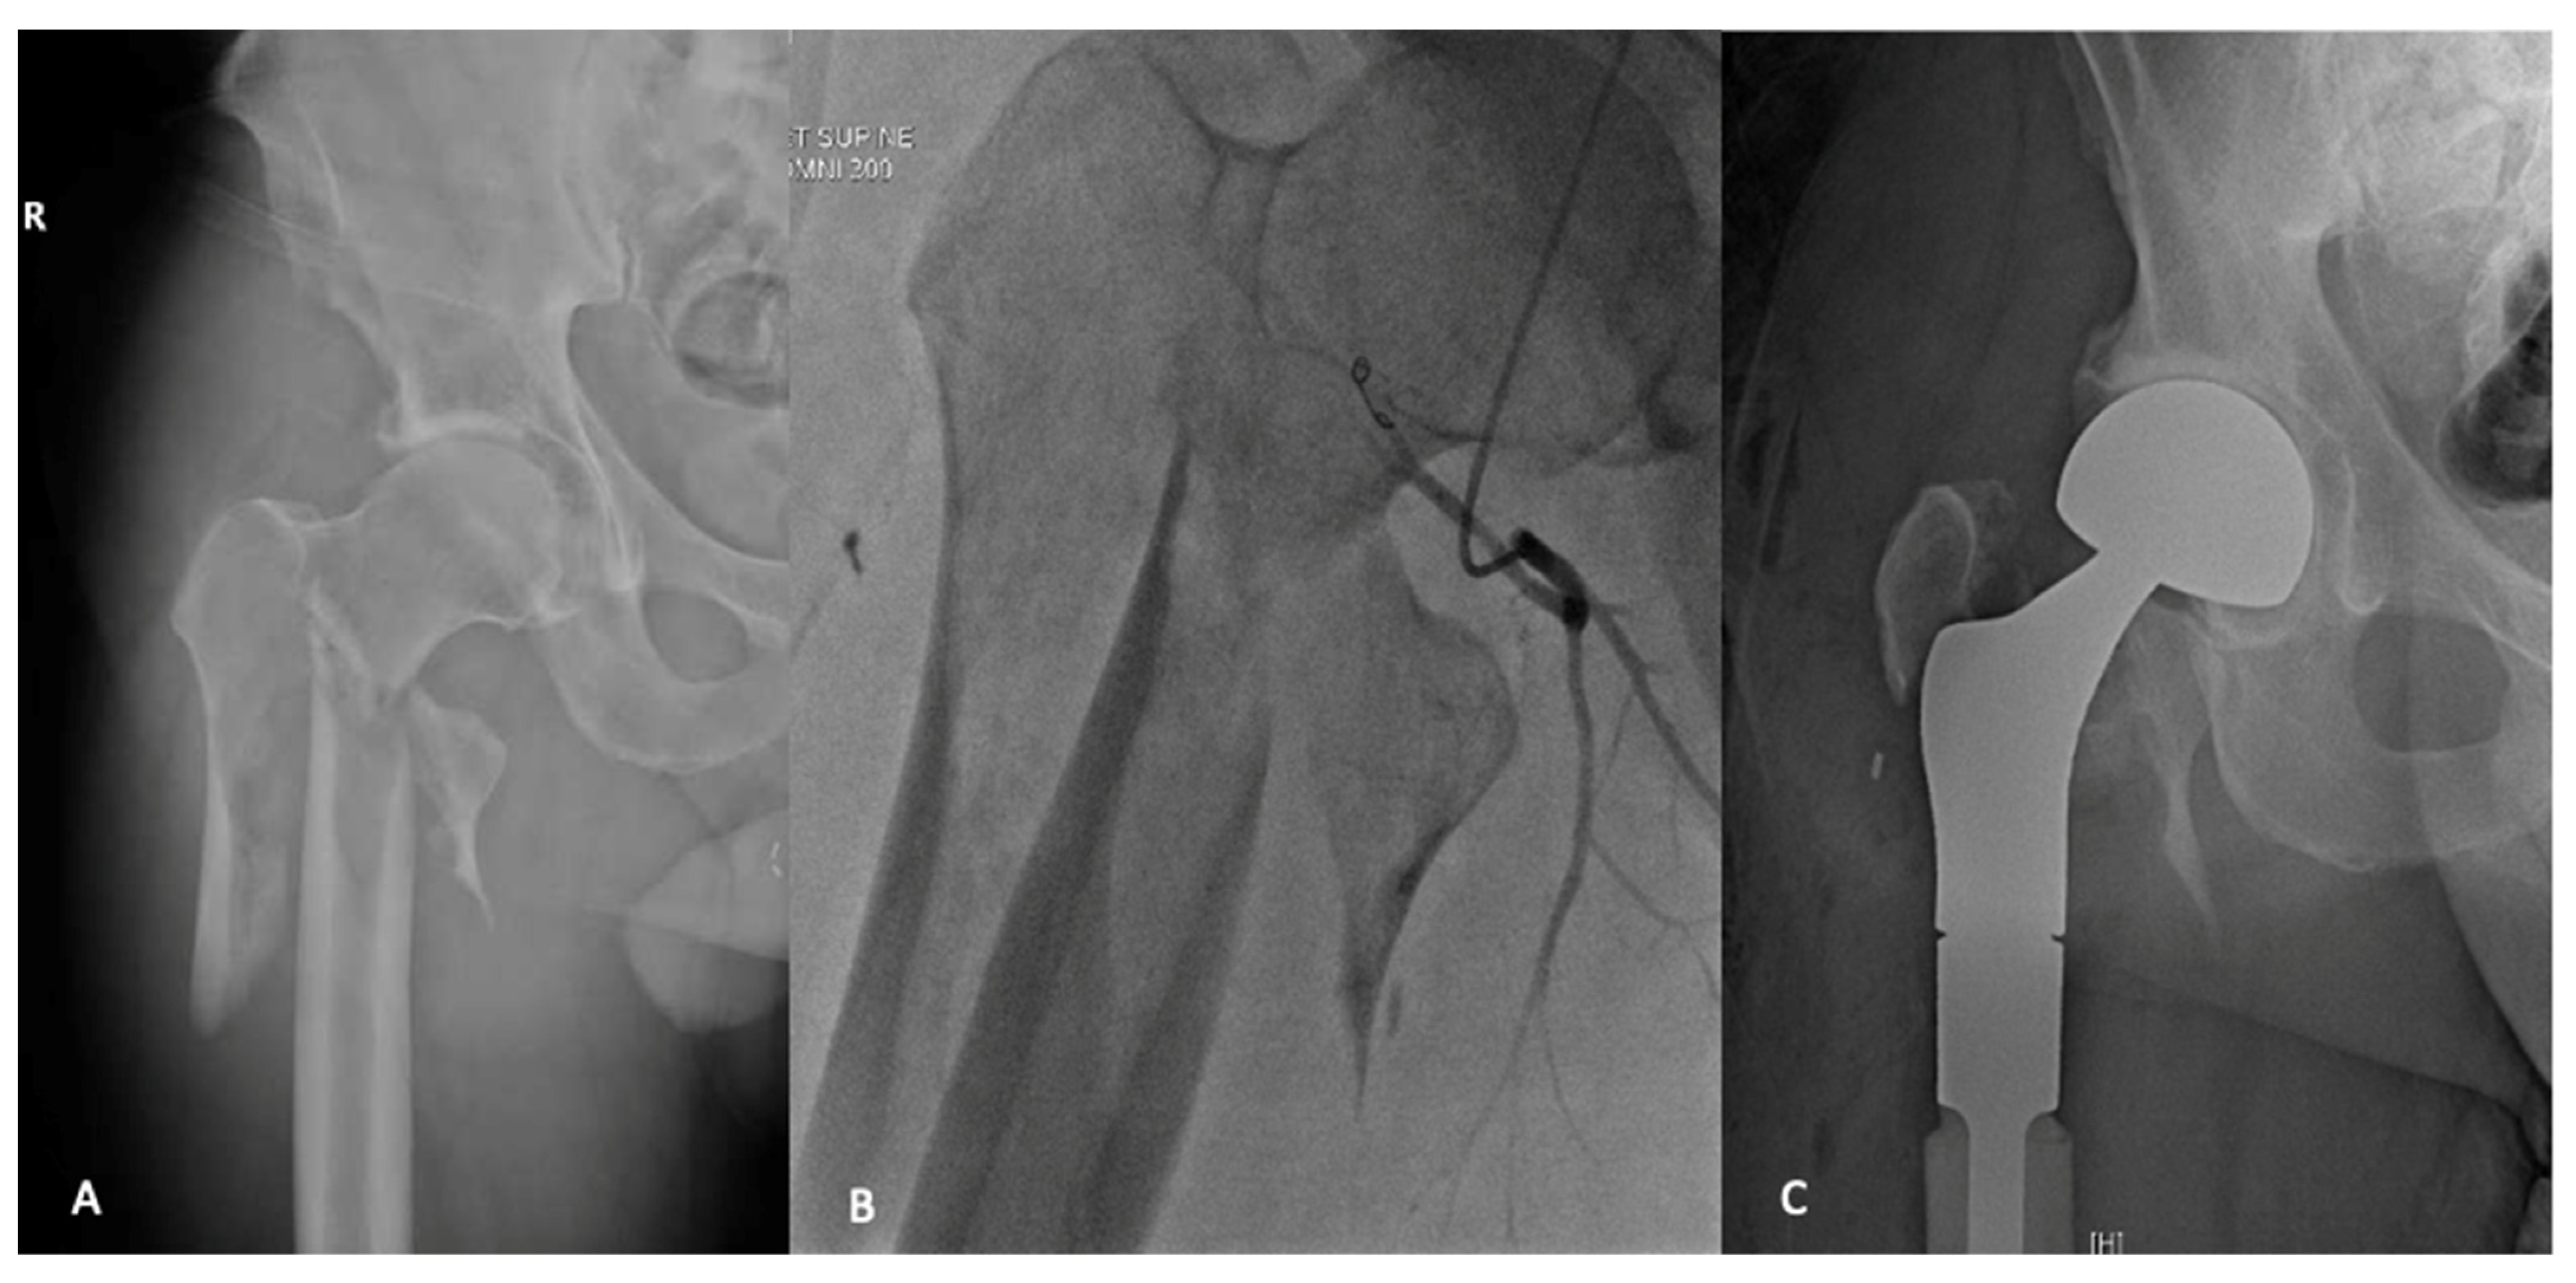

Endoprosthetic replacement may offer the best options for patients with extensive subtrochanteric bone loss. Endoprosthetic reconstructions offer a durable construct that allows for immediate weightbearing [66]. Several series have demonstrated that endoprosthetic reconstructions have improved implant survival when compared to IMN [57,66,67]. Harvey et al. evaluated 158 patients with proximal femur metastases extending into the subtrochanteric region [66]. They demonstrated similar functional outcomes and complications but improved implant longevity and reduced mechanical failure in the endoprosthetic group. The majority of orthopaedic oncologists recommend endoprosthetic reconstruction over IMN in patients with prolonged life expectancy [68]. A previous series of pathologic long bone fractures noted that the most important risk factor for implant failure was increased postoperative survival [55,69]. Endoprosthetic reconstructions also offer a reliable salvage operation in the setting of a failed fixation for pathologic fractures [44]. Finally, as mentioned previously, there is a growing movement that suggests that solitary lesions in patients with favourable histology and good overall prognosis may benefit from wide resection and reconstruction with an endoprosthesis (Figure 2) [70].

Figure 2.

A 49-year-old male who presented with a pathologic fracture through an extensive lytic lesion in the pertrochanteric and subtrochanteric region (A). Staging and workup found this to be an isolated renal cell carcinoma metastases. Preoperative angio-embolization was undertaken (B), and the metastatic deposit was treated with en-bloc resection and reconstruction with proximal femoral replacement (C).